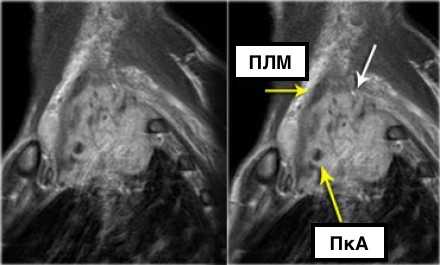

На Т1-изображениях представлен пациент с раком Панкоста Т3-стадии в связи с тем, что поражены корешки только Th1, Th2

- ПкА = подключичная артерия,

- ПЛМ = передняя лестничная мышца.

(Courtesy of Wouter van Es, MD. St. Antonius Hospital Nieuwegein, The Netherlands)

На данном постконтрастном Т1-изображении представлена неоперабельная опухоль (T4) Панкоста.

Заметна инвазия в плечевое сплетение (белая стрелка) и инвазия в подключичную артерию (а).